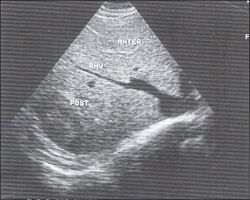

6.Сегментарное строение печени при ультразвуковом исследовании. Сегментарное строение печени - важная часть ультразвукового исследования, поскольку информация о том, в каком сегменте органа располагается поражение имеет большое значение. Печень может быть разделена печеночными венами следующим образом: правая вена делит правую долю на два сегмента - задний и передний (рис. 10) и левая вена разделяет левую долю на латеральный и медиальный сегменты (рис. 11). Теперь, если мы проведем продольные плоскости через левую, среднюю и правую главные воротные вены (рис. 12), то печень будет разделена на восемь сегментов (рис. 13).